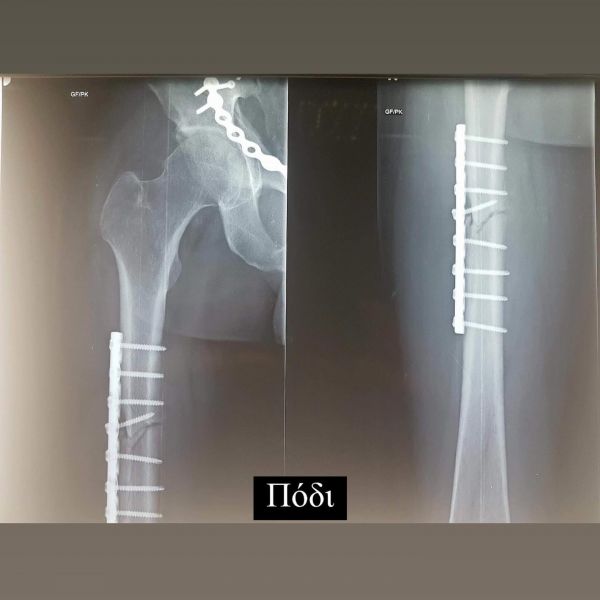

Σήμερα συμπληρώνονται 6 χρόνια από το τροχαίο ατύχημα που είχε ο Ηλίας Βρεττός και δημοσίευσε πρώτη φορά φωτογραφίες από τις ακτινογραφίες που του έκαναν και δείχνουν τα σίδερα που έχει σε χέρι, πόδι και λεκάνη.

Τα σίδερα μέσα μου που για πρώτη φορα σας δείχνω στα X-rays έτσι κι αλλιώς δεν με αφήνουν να ξεχαστώ. Όμως είμαι καλά και κυρίως είμαι εδώ!

Οι ακτινογραφίες που του έκαναν και δείχνουν τα σίδερα που έχει σε χέρι, πόδι και λεκάνη